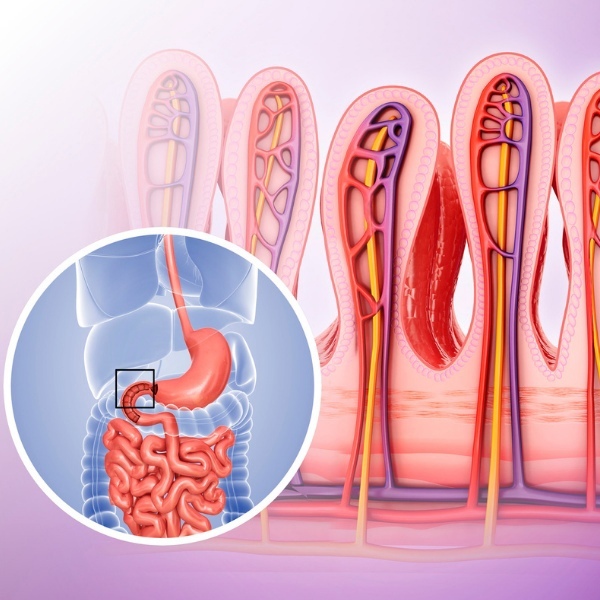

- Особенности строения слизистой оболочки тонкой кишки: ворсинки, крипты, эпителий, его клеточный состав. Различия в строении двенадцатиперстной, тощей, подвздошной кишки. Морфологическая характеристика толстой кишки, клеточный состав эпителия крипт. Лимфоидная ткань тонкой и толстой кишки.

Механизмы переваривания и всасывания в ЖКТ. Переваривание углеводов, белков и жиров. Основные механизмы всасывания. Особенности всасывания веществ в различных отделах ЖКТ.